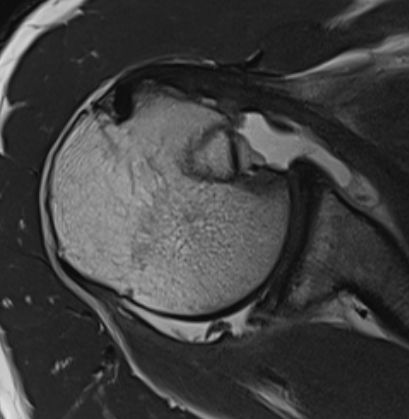

MRI

Acute MRI demonstrating reverse Hill Sachs and posterior labral tear